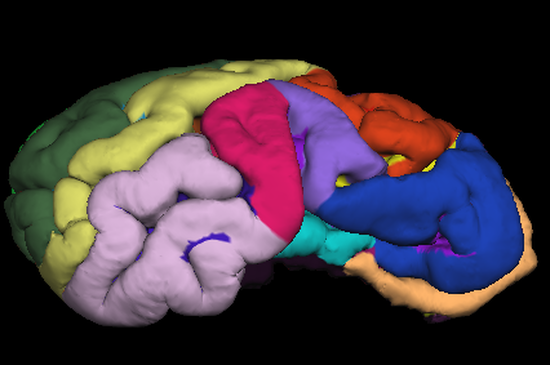

Magnetic resonance imaging (MRI) is a non-invasive technique that requires the participant to be completely motionless. To date, MRI in awake and unrestrained animals has only been achieved with humans and dogs. For other species, alternative techniques such as anesthesia, restraint and/or sedation have been necessary. Anatomical and functional MRI studies with sheep have only been conducted under general anesthesia. This ensures the absence of movement and allows relatively long MRI experiments but it removes the non-invasive nature of the MRI technique (i.e., IV injections, intubation). Anesthesia can also be detrimental to health, disrupt neurovascular coupling, and does not permit the study of higher-level cognition. Here, we present a proof-of-concept that sheep can be trained to perform a series of tasks, enabling them to voluntarily participate in MRI sessions without anesthesia or restraint. We describe a step-by-step training protocol based on positive reinforcement (food and praise) that could be used as a basis for future neuroimaging research in sheep. This protocol details the two successive phases required for sheep to successfully achieve MRI acquisitions of their brain. By providing structural brain MRI images from six out of ten sheep, we demonstrate the feasibility of our training protocol. This innovative training protocol paves the way for the possibility of conducting animal welfare-friendly functional MRI studies with sheep to investigate ovine cognition.

The psychoendocrine evaluation of lamb development has demonstrated that maternal deprivation and milk replacement alters health, behavior, and endocrine profiles. While lambs are able to discriminate familiar and non-familiar conspecifics (mother or lamb), only lambs reared with their mother develop such clear social discrimination or preference. Lambs reared without mother display no preference for a specific lamb from its own group. Differences in exploratory and emotional behaviors between mother-reared and mother-deprived lambs have also been reported. As these behavioural abilities are supported by the brain, we hypothesize that rearing with maternal deprivation and milk replacement leads to altered brain development and maturation. To test this hypothesis, we examined brain morphometric and microstructural variables extracted from in vivo T1-weighted and diffusion-weighted magnetic resonance images acquired longitudinally (1 week, 1.5 months, and 4.5 months of age) in mother-reared and mother-deprived lambs. From the morphometric variables the caudate nuclei volume was found to be smaller for mother-deprived than for mother-reared lambs. T1-weighted signal intensity and radial diffusivity were higher for mother-deprived than for mother-reared lambs in both the white and gray matters. The fractional anisotropy of the white matter was lower for mother-deprived than for mother-reared lambs. Based on these morphometric and microstructural characteristics we conclude that maternal deprivation delays and affects lamb brain growth and maturation.